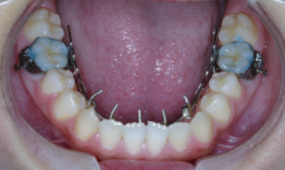

| 装置名 | マルチブラケット装置、顎急速拡大装置、タングクリブ(舌突出防止装置) |

上顎の歯の並びが狭いことに対して10歳という年齢から骨格的な拡大を見込み、上顎急速拡大装置を用いて約10mm拡大、舌の癖に対しては口腔筋機能療法(MFT)、発音トレーニングの徹底を行い舌の癖の改善を図ります。舌の位置異常の改善度を再評価しタングクリブ(舌が前に出るのを防止する装置)の装着も検討します。開咬、歯列不正に対しては第二大臼歯(12歳臼歯)の萌出度合いを確認し、マルチブラケット装置にて改善を図ります。

上顎・正面・下顎

- 治療前

- 治療中

- 治療後